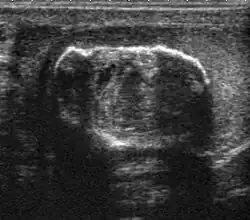

Teratoma Although teratoma is the second most common testicular tumor in children, it affects all age groups. Mature teratoma in children is often benign, but teratoma in adults, regardless of age, should be considered malignant. Teratomas are composed of all three germ cell layers, i.e. endoderm, mesoderm and ectoderm. At ultrasound, teratomas generally form well-circumscribed complex masses. Echogenic foci representing calcification, cartilage, immature bone and fibrosis are commonly seen [Fig. 5]. Cysts are also a common feature and depending on the contents of the cysts i.e. serous, mucoid or keratinous fluid, it may present as anechoic or complex structure [Fig. 6].

Fig. 5. Teratoma. A plaque-like calcification with acoustic shadow is seen in the testis. -

Fig. 6. Mature cystic teratoma. (a) Composite Image. Mature cystic teratoma in a 29-year-old man. Longitudinal sonography image of the right testis shows a multilocular cystic mass. (b) Mature cystic teratoma in a 6-year-old boy. Longitudinal sonography of the right testis shows a cystic mass containing calcification with no obvious acoustic shadow.